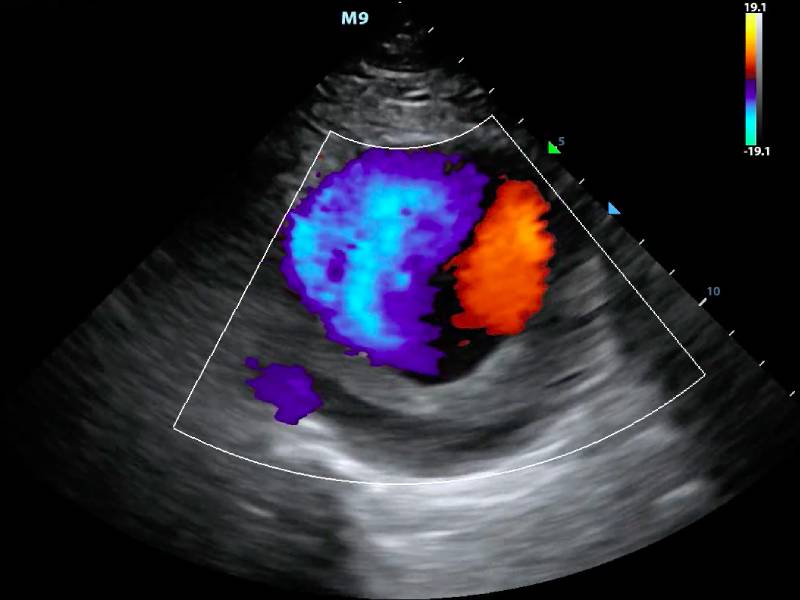

The Colour Doppler Scan was recommended to them by a family friend, who had heard of its effectiveness in diagnosing vascular issues. The scan is a non-invasive test that uses sound waves to produce images of blood flow in the arteries and veins, particularly in the arms and legs. For Ramesh, this was a practical solution, a chance to confront the unknown and potentially reclaim his health.

During the procedure, Ramesh lay still, listening to the rhythmic whooshing sounds of his own blood flow. It was a surreal experience, a peek inside his own body. The scan revealed a significant blockage in one of his leg veins, a condition known as deep vein thrombosis (DVT). While the diagnosis was serious, it was a relief to finally have clarity after weeks of uncertainty and worry.